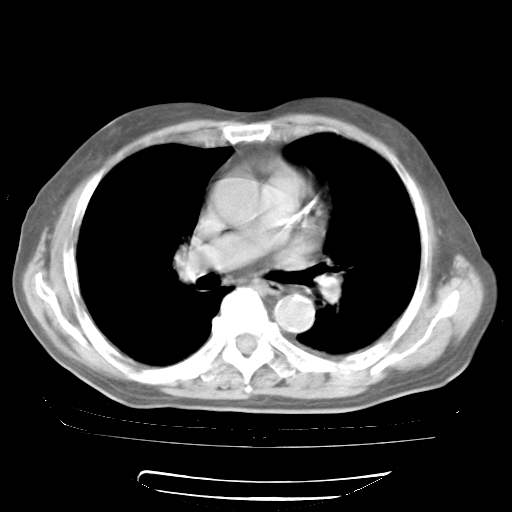

4月28日肺部CT——再次出现类似去年5月9日——透光度降低,“间质性”改变。

4月28日肺部CT——再次出现类似去年5月9日——磨玻璃样、间有“粟粒样”改变。

4月28日肺部CT